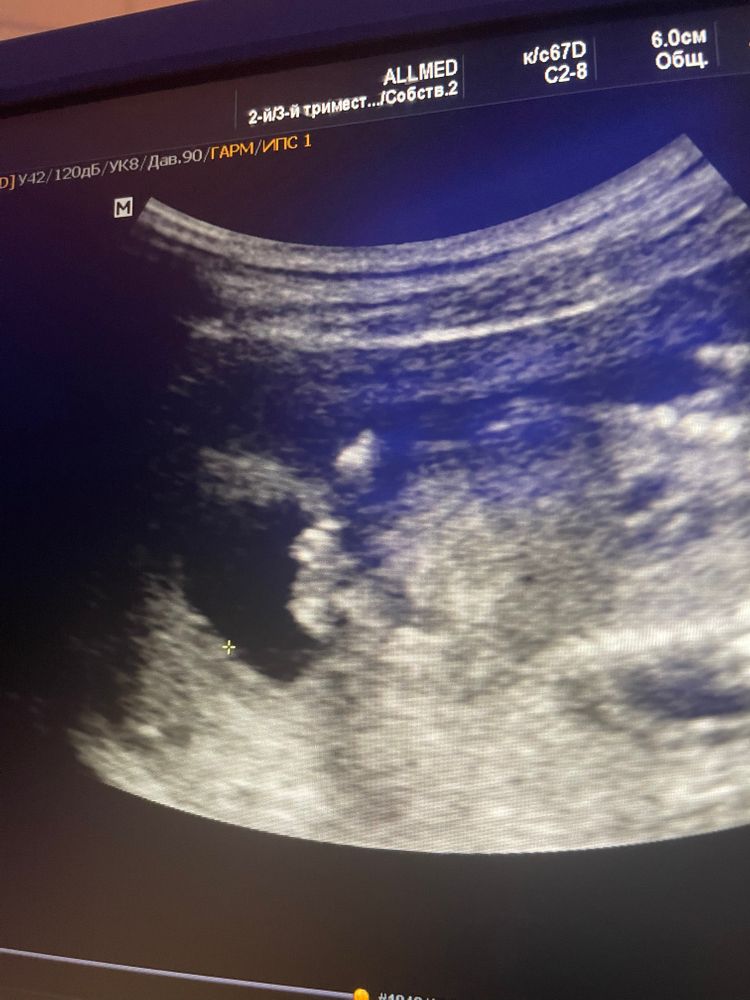

Alesyaitolik Shadrina в Здоровье будущей мамы 3 года Мамочки подскажите пол ?! Вопросы про УЗИ, обследования и анализы: что, где, как, когда? Посмотрите еще 20 записей на эту тему Отменить Ответить Маргарита А что врач говорит? Фото неоднозначное)) 10.08.2022 Ответить Alesyaitolik Shadrina Маргарита, 10.08.2022 Ответить Alesyaitolik Shadrina Маргарита, врач промолчал,говорит через месяц приходите 10.08.2022 Ответить Мама в Девочка 10.08.2022 Ответить Скай Пацан 10.08.2022 Ответить Софья Девочка. Как две миндалинки половые губы. 10.08.2022 Ответить Анна Пацан мне кажется)) 10.08.2022 Ответить Анна Пацан мне кажется)) 10.08.2022 Ответить 1 скрининг Подскажите пожалуйста пол ребёнка? Чаты Беременных Выберите чат: Январята-2026 Февралята-2026 Мартята-2026 Апрелята-2026 Майчата-2026 Июнята-2026 Июлята-2026 Августята-2026